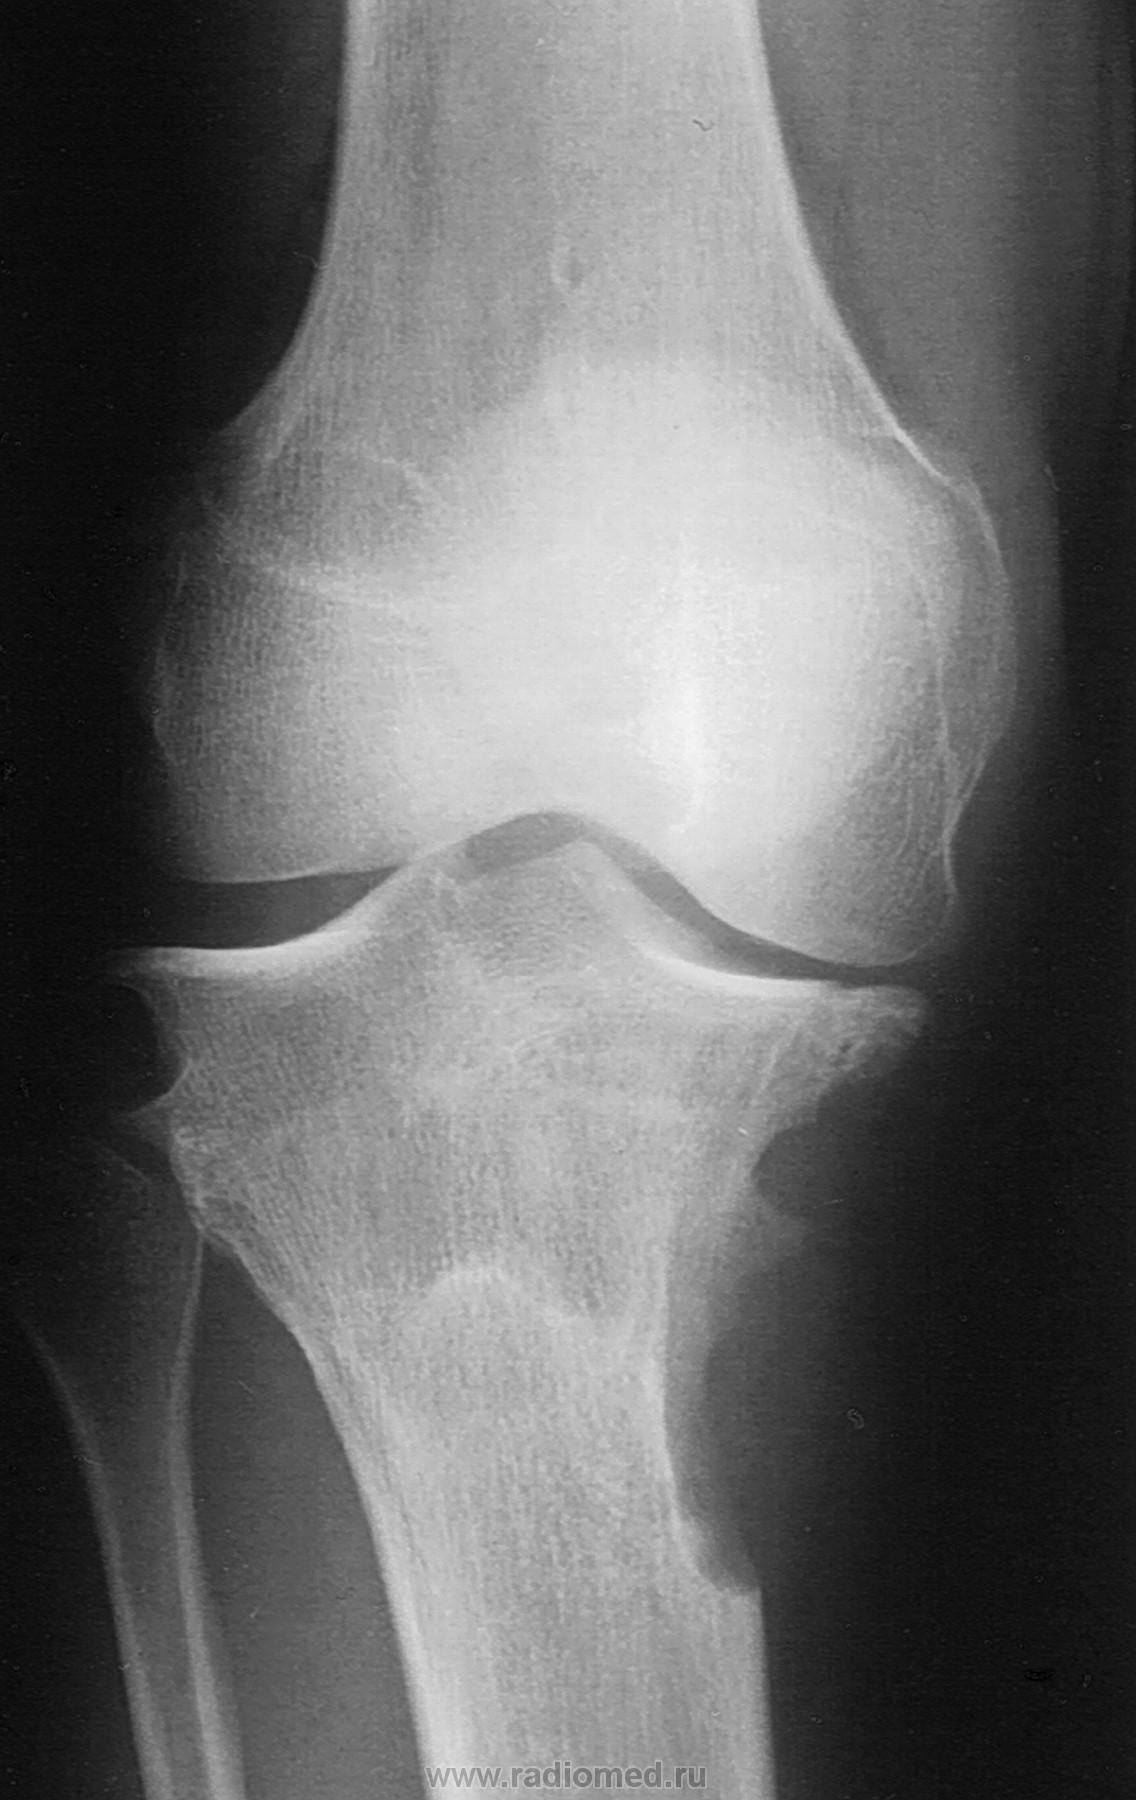

Боли в коленном суставе около двух лет.

При осмотре размеры не изменены, видна какая то "синюшность".

- синовиальная гемангиома, но изображения - завтра.

Здравствуйте, Валентин Львович! Пошла искать, нашла вот что: "Синовиальная гемангиома — редкая форма очаговой пролиферации кровеносных сосудов синовиальных оболочек суставов или суставных сумок. Ряд авторов относят ее к мальформациям. У детей и подростков обычно поражается коленный сустав, в котором возникают отек, боль и гемартроз. Реже процесс локализуется в локтевом суставе или суставах кисти. Как правило, поражение напоминает кавернозную гемангиому, реже оно имеет сходство с ангиомами капиллярного или артериовенозного типа. В любом случае пролиферируюшие сосуды выявляются сразу под поверхностью синовиальной оболочки. В этой зоне видны также очаги рубцевания и отложения гемосидерина. В запущенных случаях отмечается виллезная гиперплазия синовиальной оболочки." - http://medicalplanet.su/oncology/44.html

Поясните. А на основании чего поставлен такой диагноз? Не по рентгену же. Как объяснить двухсторонее краевое поражение? Как это укладывается в гемангиому..